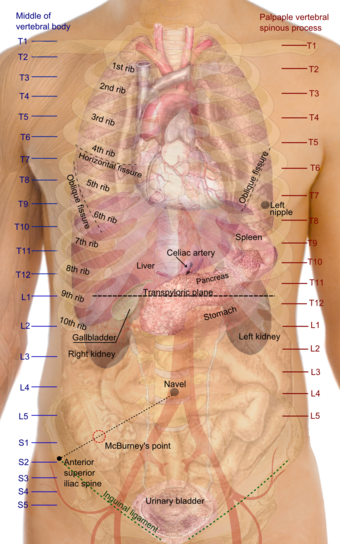

Location

In humans the kidneys are located in the abdominal cavity, more specifically in the paravertebral gutter and lie in a retroperitoneal position at a slightly oblique angle. There are two, one on each side of the spine. The asymmetry within the abdominal cavity caused by the liver typically results in the right kidney being slightly lower than the left, and left kidney being located slightly more medial than the right. The left kidney is approximately at the vertebral level T12 to L3, and the right slightly lower. The right kidney sits just below the diaphragm and posterior to the liver, the left below the diaphragm and posterior to the spleen. Resting on top of each kidney is an adrenal gland. The upper (cranial) parts of the kidneys are partially protected by the eleventh and twelfth ribs, and each whole kidney and adrenal gland are surrounded by two layers of fat (the perirenal and pararenal fat) and the renal fascia. Each adult kidney weighs between 125 and 170 grams in males and between 115 and 155 grams in females. The left kidney is typically slightly larger than the right kidney.